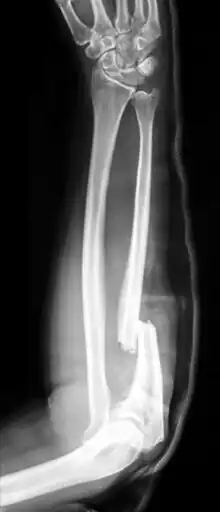

Fractures of the ulna can occur at different levels of the bone: near the wrist, in the middle or near the elbow.[2] The fracture may be confined to the ulna or accompanied with damage to the radius or the wrist or elbow joints.[2]

- Monteggia fracture - a fracture of the near to elbow end of the ulna with the dislocation of the head of the radius at the elbow joint.[2]

Monteggia Fracture (fracture of proximal ulna)